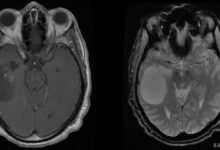

• Diğer görüntüleme testleri: Doktorunuz, tümörü ve çevresindeki alanı daha iyi değerlendirmek için manyetik rezonans görüntüleme (MRG) taraması veya bilgisayarlı tomografi (BT) taraması isteyebilir. Tümörün akciğerlere yayılıp yayılmadığını belirlemek için ilk tanı sırasında BT taraması veya göğüs röntgeni de yapılabilir.